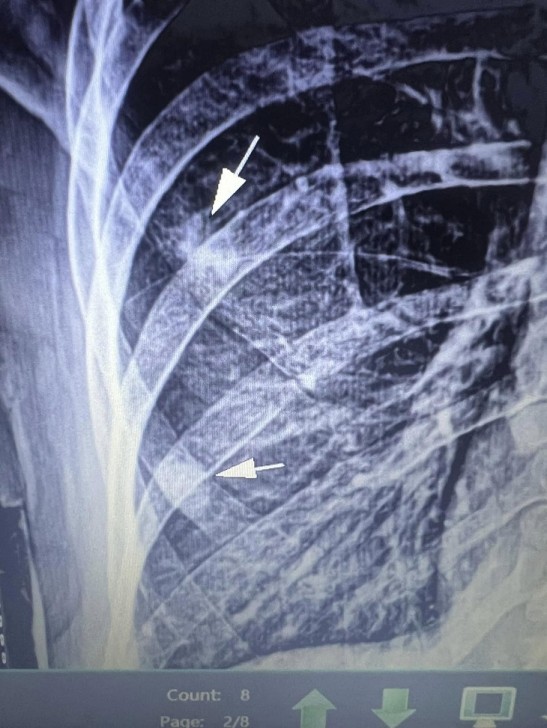

AFN.az xəbər verir ki, tanınmış həkim Aydın Əliyev bu sahədə vəziyyətin getdikcə ağırlaşdığını bildirib. O, xəstələrdən birinin müayinə nəticələrini paylaşaraq bunları yazıb: “Onkoloji xəstəliklərin müayinə və müalicəsinin hələ də icbari tibbi sığorta tərəfindən qarşılanmamasının daha bir qurbanı. Sağ qamış sümüyündəki törəmənin maddi imkansızlıq səbəbindən vaxtında və sistemli müalicə və ya əməliyyat edilməməsi səbəbindən fəqərələrə, qabırğalara, kürək, çanaq sümüklərinə, ağciyərə çoxsaylı metastazları. Demək olar ki, adam həyatını itirib”.